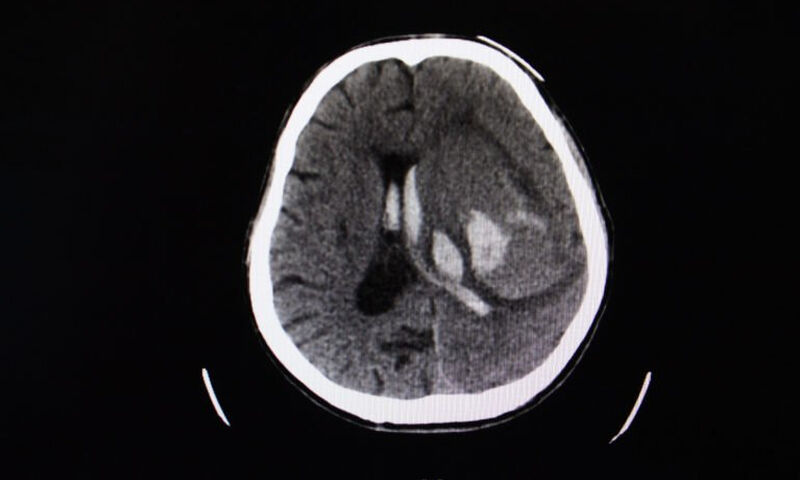

Η ρήξη του ανευρύσματος προκαλεί έξοδο του αίματος στη βάση του εγκεφάλου (λίγο κάτω από το επίπεδο των ματιών). Αυτό αποτελεί έναν επικίνδυνο τύπο εγκεφαλικής αιμορραγίας που ονομάζεται υπαραχνοειδής αιμοραγία (διάχυτη αιμορραγία έξω από τον εγκέφαλο). Μπορεί επίσης να προκληθεί ενδοεγκεφαλικό αιμάτωμα (αιμορραγία μέσα στον εγκέφαλο), ή τέλος ενδοκοιλιακή αιμορραγία (μέσα στο κοιλιακό σύστημα του εγκεφάλου).